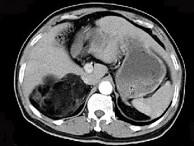

问题 男,59岁,右侧腰背酸痛,CT检查如图所示,应诊断为()

选项 A.右肾上腺腺瘤 B.右肾上腺转移瘤 C.右肾上腺髓样脂肪瘤 D.右腹膜后脂肪瘤 E.右肾血管平滑肌脂肪瘤

答案 C